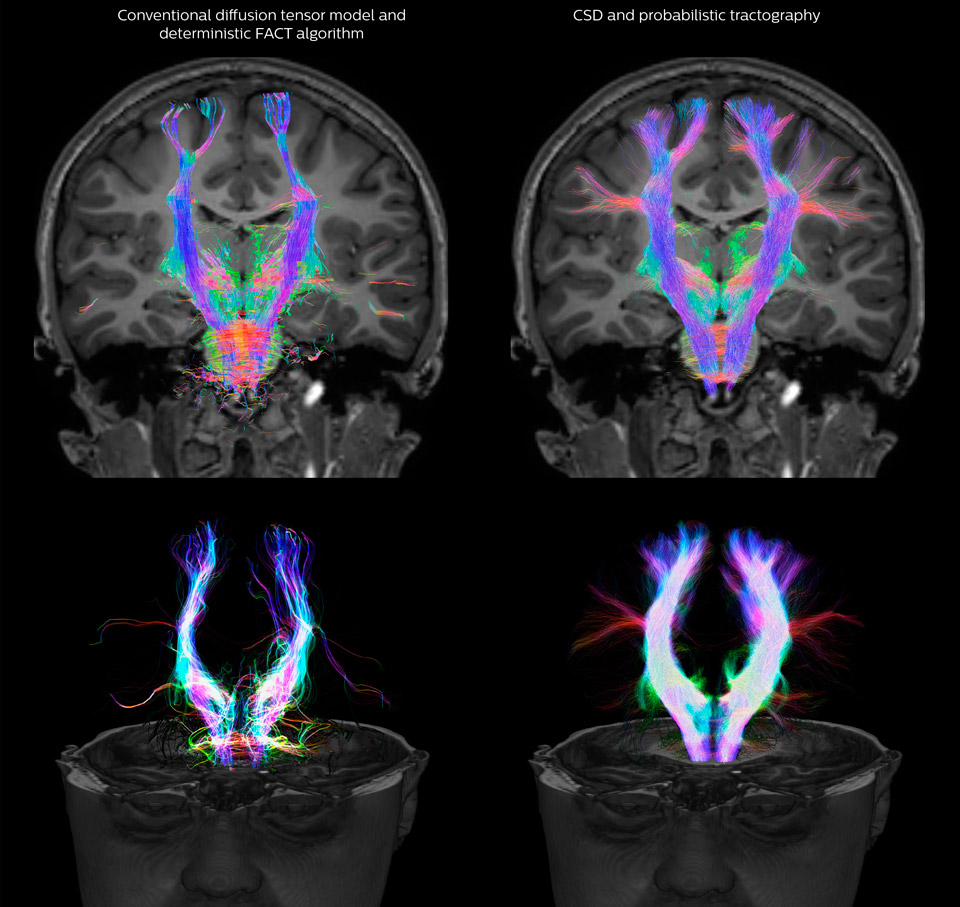

Fiber tractography of the corticospinal tract with seed region of the posterior limb of the internal capsule. Different processing based on the same data.

All images were created from the same acquisition in a child using Ingenia 3.0T CX and 32-channel dS Head coil. Diffusion data was acquired at b-values 0, 500, 1000, 2000, 3000. The use of high b-values (3000 s/mm2) effectively suppresses extra-axonal water signal and provides high angular resolution.

Legend of acronyms

CSD: constrained spherical deconvolution

DEC TDI: directionally encoded color track-density imaging

DTI: diffusion tensor imaging

DWI: diffusion-weighted imaging

FOD: fiber orientation density

Data processing was performed using open source software. Fiber tracking was performed using the MRtrix package (J-D Tournier, Brain Research Institute, Melbourne, Australia, https://github.com/MRtrix3/mrtrix3), Tournier et al. 2012. DEC TDI based on F Calamante et al 2010.

CSD of multishell DWI results in the white matter FOD at each voxel. Unlike the conventional diffusion tensor model, this approach enables accurate modeling of multiple fiber populations within a single voxel.